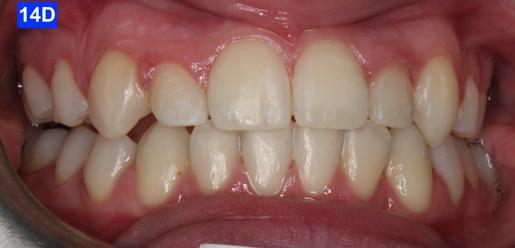

Please view the post-treatment images at the time of insertion of the retainers (Figure 14 - A, B, C. D, E, F, G, H, I, J, K, L, M, N).9

Figure 14D: Post-treatment frontal view

Figure 14E: Post-treatment, right lateral view

Figure 14F: Post-treatment, left lateral view

Figure 14G: Post-treatment, occlusal view

Figure 14J: Post-treatment, posture, frontal view

Figure 14K: Post-treatment, posture, lateral view

Figure 14L: Post-treatment, frontal view

Figure 14M: Post-treatment, lateral view

Figure 14N: Post-treatment, posed smile

Although the treatment was a lengthy one (60 months), our outcome was favourable. The patient was finished with a skeletal class I, an Angle Class I cuspid and a Class II molar relationship with minimal overjet and overbite. ANB stayed the same however, Wits improved from -5.0 mm to 2.0 mm. ALFH increased by 7.0 mm due to the composite build-ups on the mandibular first molars and elevation of the rest of the mandibular dentition to this height. Also, the growth from CVMS 2 - 3 to CVMS 5 influenced the height of the mandibular alveolar process. The patient’s posture did not change significantly as the frontal view still revealed a slight left head tilt, and the lateral view revealed the head forward position seen previously. We postulate that the lack of greater improvement in posture relates to untreated nasal airway impingement. Olmos writes that nasal airway compromise is thought to exacerbate forward head posture, worsen unfavourable growth patterns (hyperdivergence) and contribute to mouth breathing as the patient is attempting to maintain a better airway.10 It is possible that advancement of the maxilla may have

The position of the anterior teeth was more favourable, U1/SN 93° to 109°, L1/GoM 83° to 91°. The Naso-labial angle became more obtuse from 110° to 118°. The Facial axis (Growth axis –Ricketts) changed to a more ideal value, from 83° to 92°, due to the odontectomy of two maxillary first bicuspids.

The final panoramic radiogram reveals impacted wisdom teeth and distally tipped mandibular second molars that partially erupted. The final periapical radiograms of the maxillary anterior teeth reveal minimal root resorption and acceptable angulation except for #12(7), where the root remained distally oriented.

Concerning the finishing and esthetics, the patient would have benefited from more detailing and refinement but after 60 months of treatment she was exhausted. She expressed great satisfaction with her outcome and we felt the occlusion was acceptable. Therefore, given the understandable treatment fatigue, the patient’s expression of appreciation towards her result, and the functional success, we agreed to end the treatment.